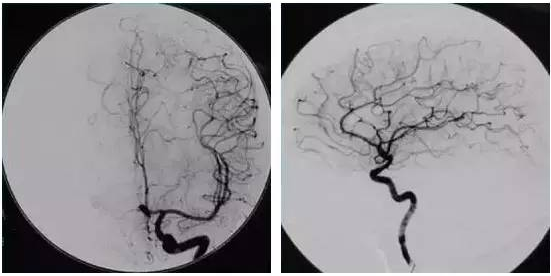

中风病科(神经内科)是全国重点农村医疗机构特色中医专科,齐鲁中医药优势专科集群建设单位,潍坊市重点中医专科。 科室人员组成 现有医护人员18人,其中医师7名(副主任医师1名,主治医师4名,医师2名;研究生4名);护士10名(副主任护师1名,主管护师1名,护师4名,护士4名);中级康复师1名。 业务范围 1.科室主要业务为急性期(2周内)脑中风,包括脑梗死、脑出血;运用“卒中单元”的治疗模式治疗中风病,开展急性缺血性脑卒中超急性期静脉溶栓治疗,脑血管造影、颈部血管支架植入术。 【脑血管造影】是诊断脑血管疾病的金标准,对于缺血性脑血管病,可清楚地显示动脉管腔狭窄、闭塞、侧支循环建立情况等,对于脑出血、蛛网膜下腔出血,可进一步查明导致出血的病因,如动脉瘤、动静脉畸形、动静脉瘘等。 【静脉溶栓】是通过静脉血管注射溶栓药物把血管内堵塞的血栓溶解掉,从而使被阻塞的血管再通,恢复血流,挽救尚未死亡的细胞。 【颈内动脉支架置入术】对于症状性狭窄达到50%,或者非症状性狭窄达到70%,行颈内动脉支架置入,可以预防脑卒中。 2.各种神经系统疾病,如头痛、头晕、失眠、癫痫、帕金森病、运动神经元病等变性疾病、周围神经病、肌病、感染性疾病、自身免疫性疾病、遗传性疾病、中毒性疾病、营养缺陷和代谢障碍性疾病等的内科治疗。 中医特色 1. 专科制剂:发挥中药治疗中风病特长,研制了“通络化痰汤、眩晕方”等,在临床取得良好疗效。 2. 针灸:对于失语的病人,可以给予病灶头皮反射区压针治疗中风后失语,可以促进语言功能恢复。对于中风启吞咽困难、饮水呛咳的病人,给予项针针刺疗法,可以快速改善病人吞咽、饮水功能。 3. 中医推拿:针灸配合康复训练,促进病人肢体功能的康复,快速提高病人生活自理能力,缩短住院时间。 4.贴敷疗法:中药外敷穴位,以活血化瘀、消肿止痛,减轻肢体肿胀。 5.放血疗法、揿针:两种中医适宜技术有机结合,揿针循经选穴,调整人体阴阳,缓解头晕头痛,改善睡眠等。 6.艾灸:利用艾柱的特性和间隔物的药力发挥协同作用,达到活血化瘀,疏通经络的目的,改善卒中后肢体麻木疼痛、痿软无力等症状。 7.八段锦:用我国古老的中医养生操八段锦,促进卒中病人的康复。 病例分享 ↑↑↑点击链接,了解详情↑↑↑ 专家资源 外聘专家 李衍滨,山东第一医科大学第一附属医院(山东省千佛山医院)神经内科主任医师,医学博士,博士研究生导师,中国中西医结合学会神经科分会常委,山东省医师协会中西医结合分会副主任委员,山东中西医结合学会眩晕病专业委员会副主任委员,山东省医学会脑血管病分会委员,山东省医师协会神经介入专业委员会常委,山东省中西医结合学会睡眠医学委员会副主任委员,山东省中西医结合学会神经内科分会委员-神经介入学组组长 。 专业特长:主要研究方向为脑血管病和神经免疫性疾病。尤其擅长急性脑梗死的血管开通治疗(静脉溶栓、动脉溶栓及机械取栓)、脑动脉狭窄支架植入术,动脉瘤栓塞;头晕、头痛、睡眠障碍及重症肌无力等各类神经系统疾病的中西医结合治疗。 王法德,主任中医师,原潍坊市中医院脑病教研室主任,原潍坊市中医院院长、脑病科主任,教授,硕士研究生导师,全国先进名医工作室获得者,全国名老中医学术经验继承工作指导老师,山东省名老中医专家,潍坊市建国60周年百名时代功勋人物,潍坊市专业技术拔尖人才,潍坊名医。 专业特长:以治疗中风病、糖尿病、肾脏病为主。尤擅长治疗中风病,对中风病的治疗主张五个结合;对急、慢性肾小球炎,肾病综合症,尿路感染,尿路结石及慢性肾功能不全的治疗,亦积累了丰富的经验。 科室骨干 李德清,副主任医师,中风病科(神经内科)主任,山东省神经退行性疾病专业委员会委员,潍坊市中医药学会中风病专业委员会委员,潍坊市预防医学会眩晕疾病防治委员会委员,潍坊市健康管理协会神经病学分会委员。 擅长:脑血管病、头痛、头晕、癫痫等神经内科常见病的诊治。特别“耳石症”手法复位治疗疗效显著。 手机:15966189052 王文明,硕士研究生,主治中医师,中风病科副主任,山东省卒中学会中医分会委员,潍坊市中风病委员会委员。 擅长:中医药治疗中风,眩晕,头痛,失眠,疲劳综合征及情志病。 手机:15169579156 欧森梅,主治医师,潍坊市中风病专业委员会委员,眩晕疾病防治专委会委员。 擅长:多年从事脑血管病,眩晕,头痛,癫痫,失眠等疾病的诊治,拥有丰富的临床治疗经验。 手机:15169468990 供稿:中风病科 编辑:姚春雨 责编:宋美爱 审核:刘国华